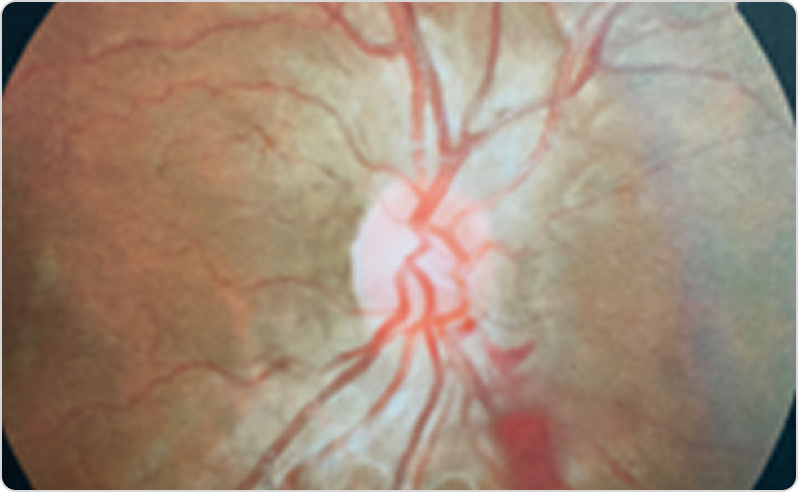

Фабри ауруы кезіндегі тамырлық өзгерістері бар көз түбінің фотосуретіФабри ауруы кезіндегі тамырлық өзгерістері бар көз түбінің фотосуреті

6-сурет. Оң көздің көз түбінің фотосуреті: торқабық тамырларының иректілігі (екіжақты), көру жүйкесі дискінен төменгі-мұрындық квадрантта шынытәрізді денеге аздаған қан құйылу.

Бейімделген дереккөз: Salazar P. Clin Insights Eye Care. 2023;1(1). © 2023 Salazar P. CC BY 4.0.45